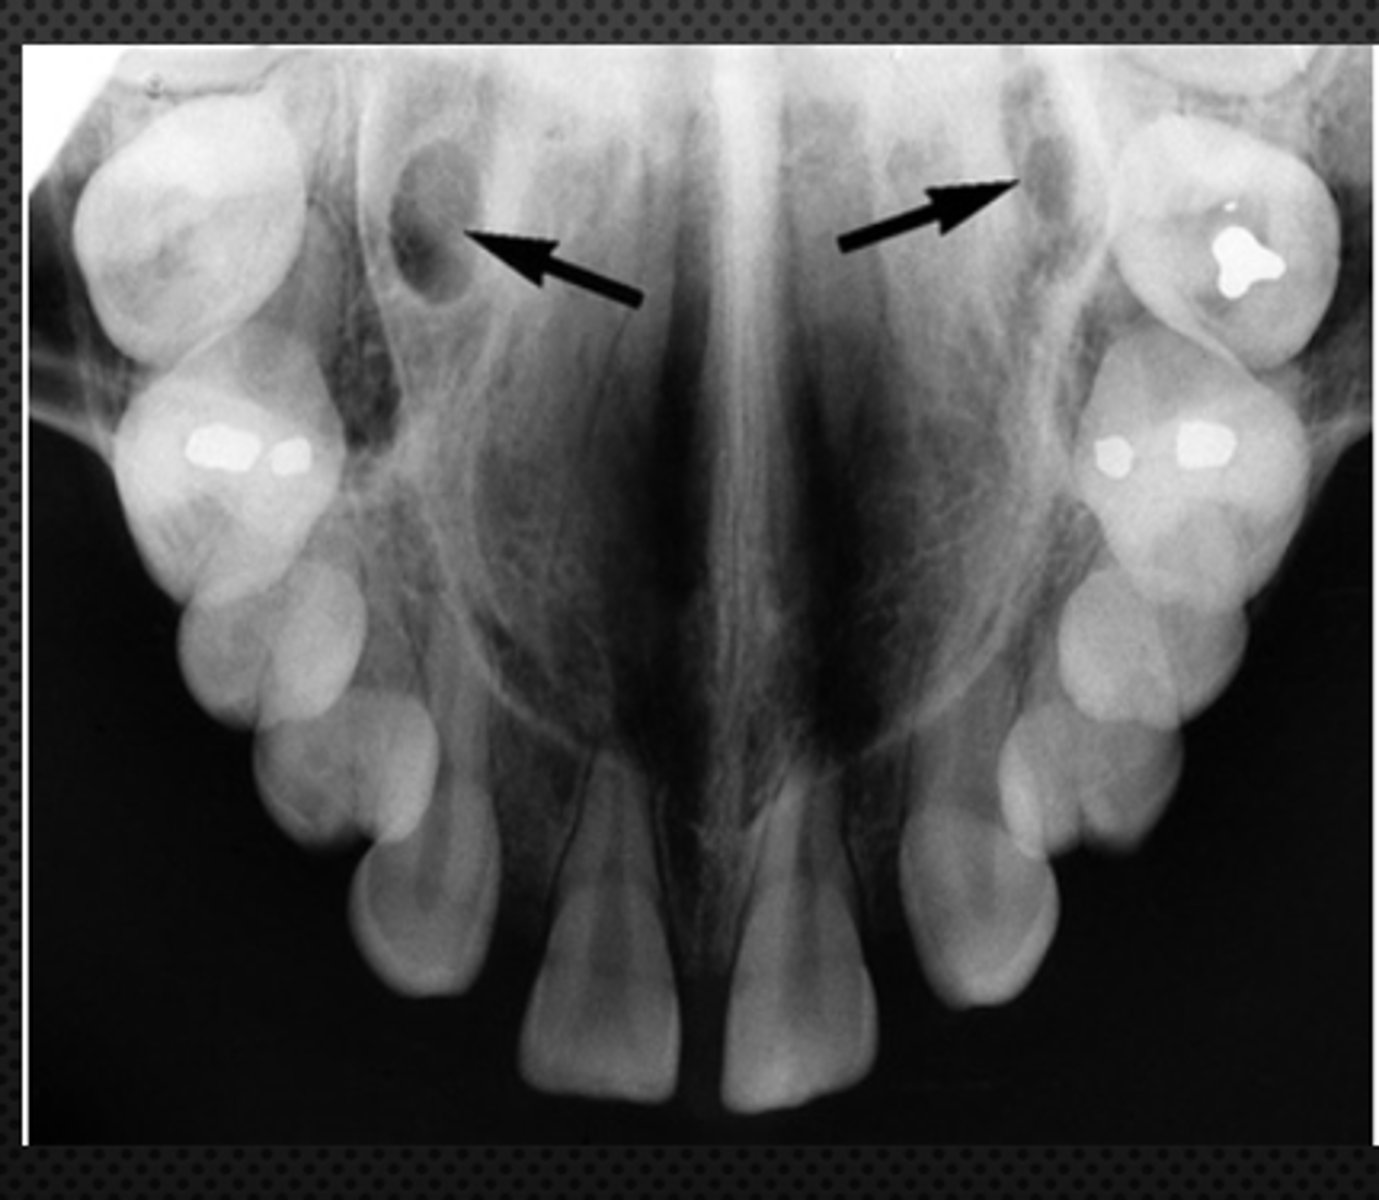

New cards

Floor of nasal cavity

Identify the structure

<p>Identify the structure</p>

7